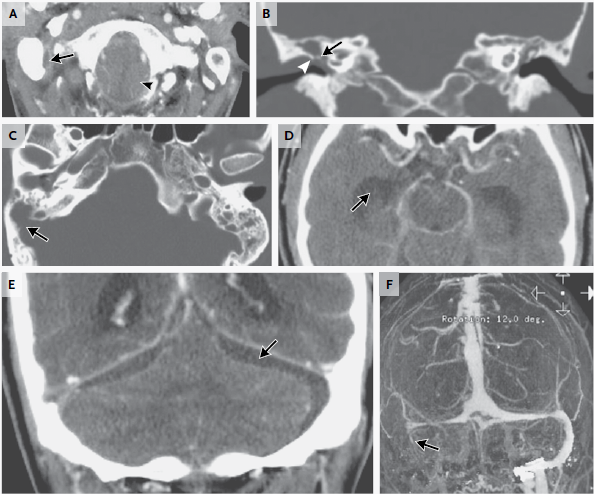

En el examen, la temperatura era de 37,4 ° C; los otros signos vitales y la saturación de oxígeno eran normales. El examen oftalmológico reveló una agudeza visual de 20/20 en el ojo derecho y 20/400 en el ojo izquierdo. Las pupilas eran iguales, redondas y reactivas, con un defecto pupilar aferente izquierdo. Resultados de las pruebas de color visión con placas de color de Ishihara fueron normales en el lado derecho (8/8 correctamente identificados) y 0/8 de la izquierda. La presión intraocular era 13 mm Hg en el lado derecho y 11 mm Hg a la izquierda. Examen con lámpara de hendidura reveló segmentos normales anteriores bilateralmente. El examen de la motilidad extraocular reveló plena movilidad en el ojo derecho; el ojo izquierdo tenía aducción limitada, supraducción y infraducción, con intorsion mínimo en intento de secuestro (Figura 2 ).

Figura 2

Fotografías de los ojos del paciente.

En la mirada primaria (Panel C) hay leve ptosis del párpado superior izquierdo.El ojo izquierdo tiene leve déficit de elevación (Panel A), aducción (Panel B), y depresión (Panel E), y no tiene abeducción (PanelD).